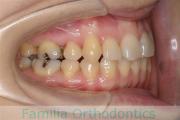

No.22V-269

- 過蓋咬合

- 上顎前突

- 20歳

- 女性

- 44

- 88

- FEA

- 90万円

左上の前歯の出っ歯が気になるということで来院されました。下あごの後退が非常に強く、外科矯正も選択肢の一つでしたが、矯正治療単独の治療をご希望になりました。上顎のみ左右小臼歯を抜歯して、マルチブラケット法を行いました。2年半、30回程度の通院が必要でした。

下あごの後退があるということは、上の前歯を大きく移動させないとかみ合わせが取れないということです。そのため、同部の歯根吸収のリスクが高いケースでした。